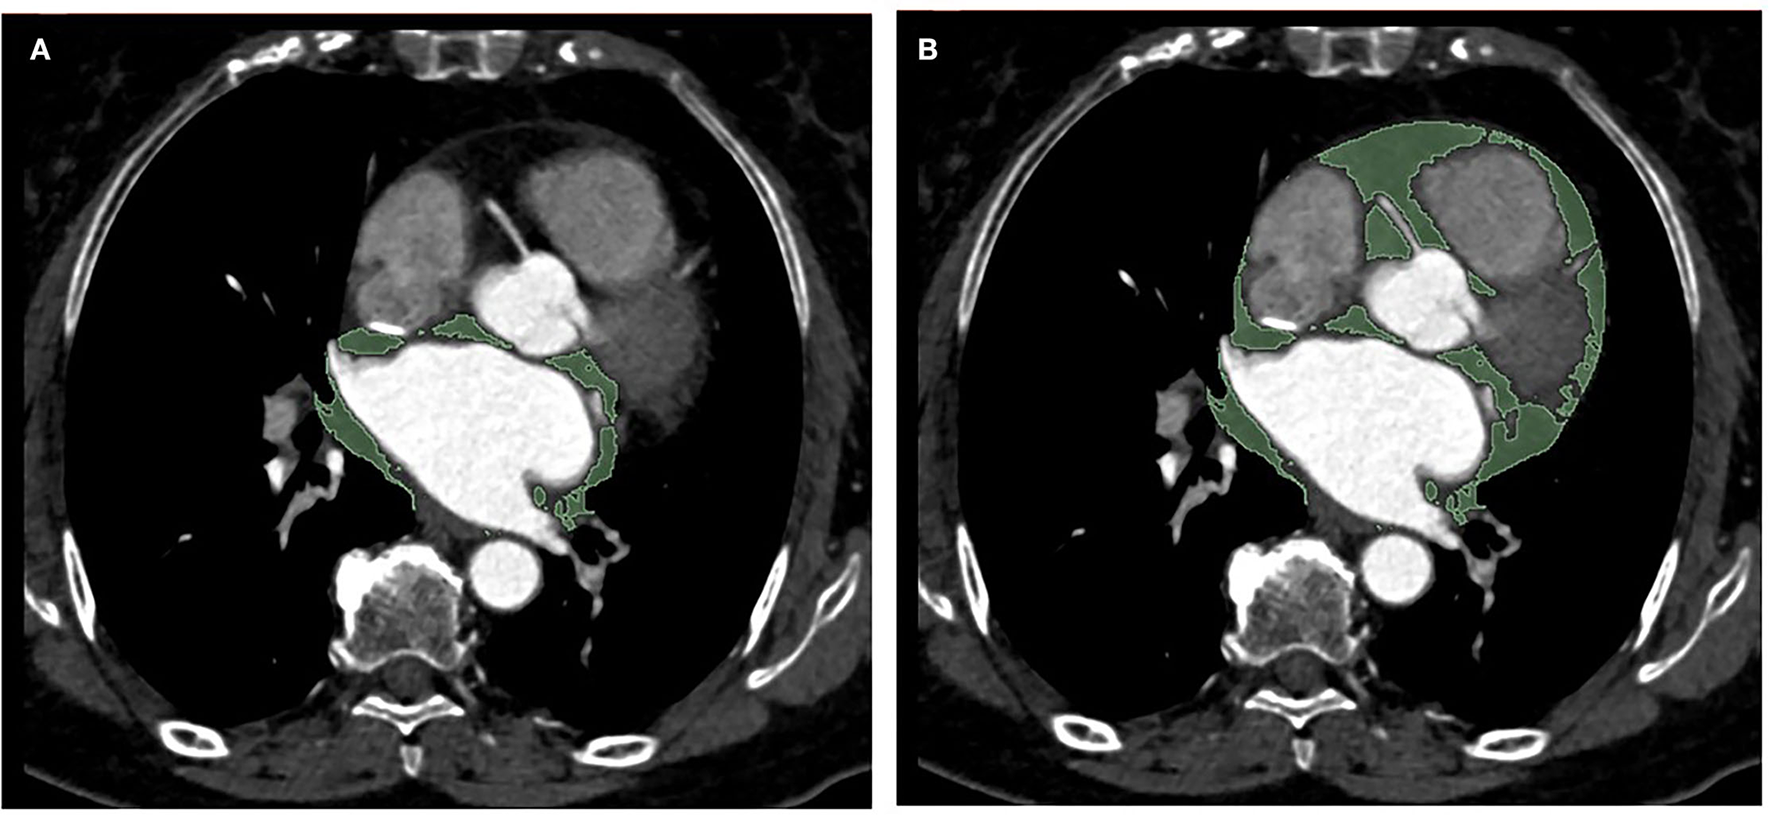

Epicardial adipose tissue volume measurement was performed with a 3D Slicer software (Boston, USA, 4.11.2 version). EAT has been defined as the adipose tissue between the pericardial visceral layer and the surface of the myocardium. The volumes of total EAT and periatrial EAT surrounding the left atrium were determined by manually tracing from the first section to the last section containing any images of the whole heart and the left atrium, respectively. The region outside the pericardium was excluded. EAT was automatically recognized using the software as tissue with HU between −195 and −15 for contrast-enhanced images as described previously (20). Subsequently, the region of interest (ROI) was examined and reviewed by the experienced operator (with 4 years of experience in cardiovascular imaging), and the voxels in the respective slice were summed to determine the total EAT volume and periatrial EAT volume (Figure 1). Moreover, the periatrial to total EAT ratios (P/T EAT ratio) of all patients were calculated. For the interobserver analysis, 50 individuals were randomly selected and then analyzed independently by two experienced radiologists (with 4 years of experience in cardiovascular imaging) blinded to clinical characteristics and CT findings. In terms of the intra-observer analysis, the results of the same 50 subjects above were measured again by one of the radiologists 2 weeks later.

Figure 1

Representative example of periatrial EAT (A) and total EAT (B) measurement in a single axial CT image in a patient (area in green depict traced EAT). EAT, epicardial adipose tissue.